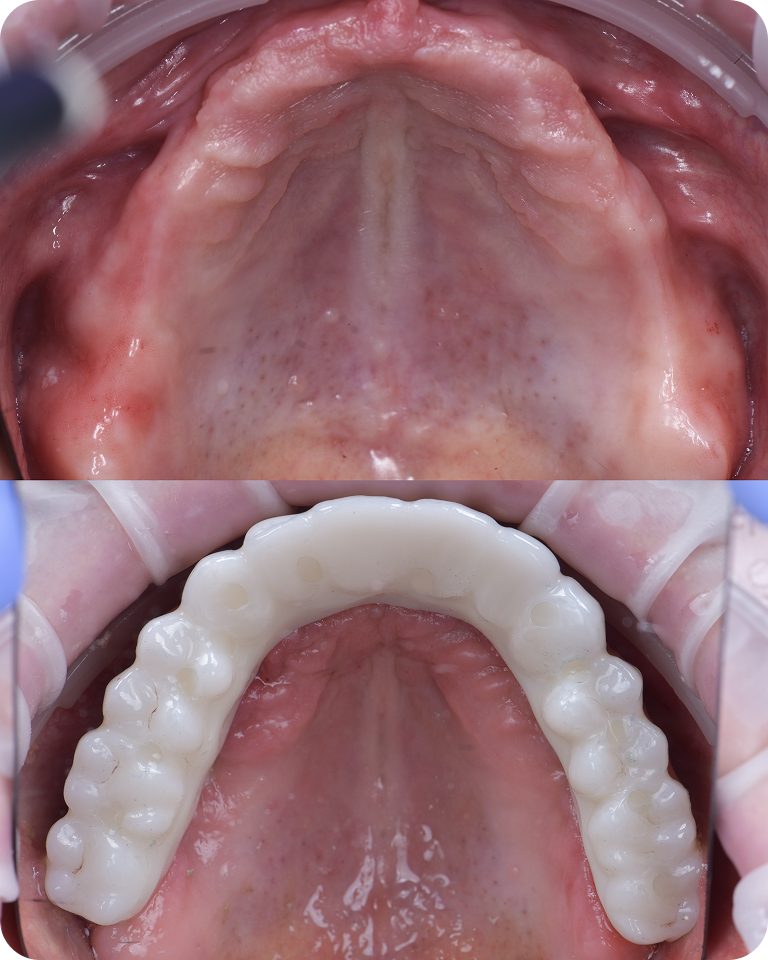

Открытое небо

Установка временного протеза

В большинстве случаев мы устанавливаем временный протез на импланты в день операции. Но не всегда это возможно. Если кость слабая, и не удалось застабилизировать импланты, то устанавливаем временный съемный протез на имплантах

После приживления имплантов через 4-6 месяцев съемный протез переводится в несъемный

Установка постоянного протеза

Через 4-6 месяцев после приживления имплантов, временные протез следует поменять на постоянный. Есть 2 вида финального протеза:

• Пластиковый. Более бюджетный протез, который следует менять каждые 3-5 лет. Стоимость 70.000 ₽

• Циркониевый. Постоянный керамический протез, который устанавливается на 15-20 лет. Стоимость 400.000 ₽